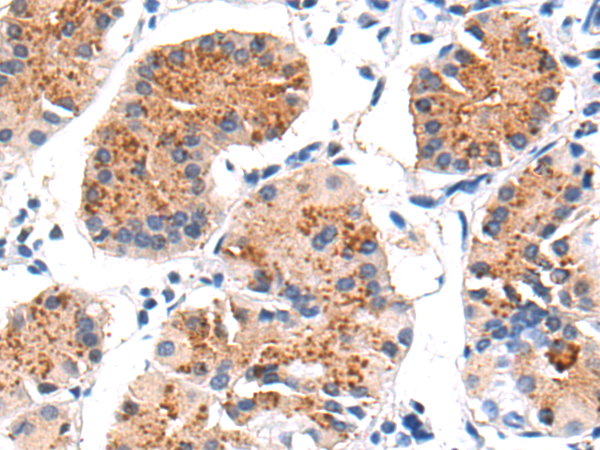

分类: 科研抗体货号: P04734别名: GVI; PLA2; INAD1; NBIA2; iPLA2; NBIA2A; NBIA2B; PARK14; PNPLA9; CaI-PLA2; IPLA2-VIA; iPLA2beta应用: IHC反应种属: Human, Mouse, Rat